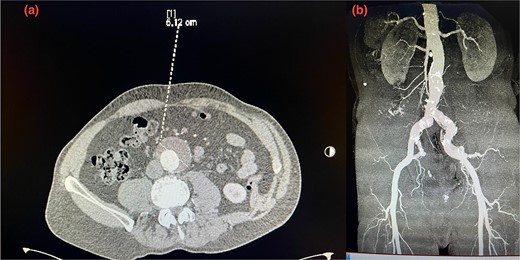

Given the anatomical complexity and the risk of injury to the hypogastric artery, we opted for EVAR, along with a flared limb extension to address the common iliac artery ectasia (Fig. 2). However, the patient experienced recurrent episodes of acute limb ischemia postoperatively, necessitating a thorough diagnostic and therapeutic approach.

Postoperative 3D reconstruction CTA image of the EVAR without any sign of endo leak.